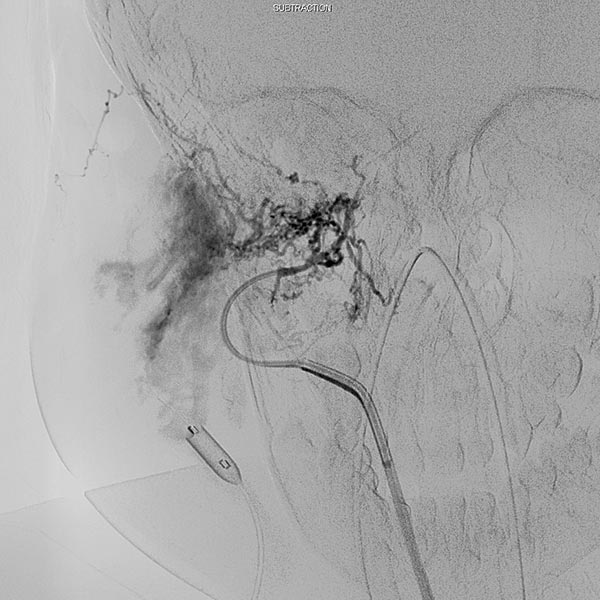

Digital subtraction angiography (DSA) after injection into the right common carotid artery shows the infantile hemangioma mainly supplied from the external carotid artery, as expected.

Digital subtraction angiography (DSA): After insertion of a 4F diagnostic catheter transarterially into the external carotid artery, selective advancement of a microcatheter into the maxillary artery. The infantile hemangioma presents as typical contrast pooling (“tumor blush”). The transvenously inserted balloon blocks the venous outflow and is clearly visible. Embolization was then carried out with particles of 150 micron size and without unintended venous outflow.